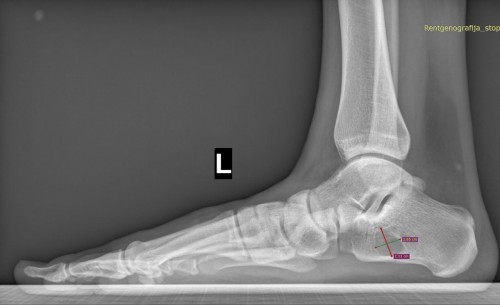

С костной кистой такого размера если сопровождается риском патологического перелома, могу претендовать на 10б-В?

DZDZ писал(а):Платный прием у взрослого травматолога-ортопеда, рентген из детской поликлиники (июль 2025), сейчас мне 18 лет.